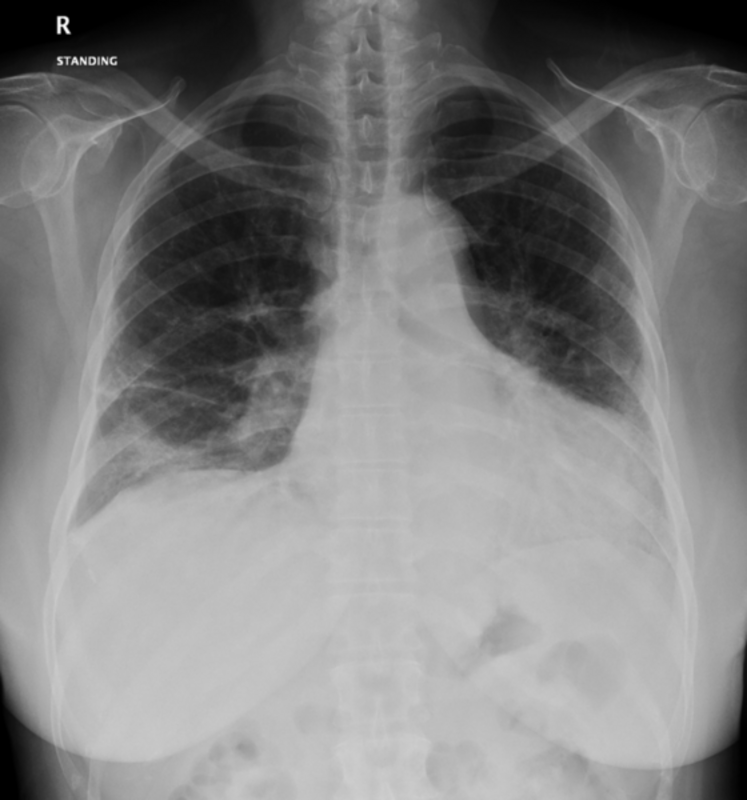

Пациенты с признаками обычной интерстициальной пневмонии при хирургической биопсии легких были, как правило, старше (57 лет против 53 лет; P = .042) и имели предшествующее заболевание легких до заражения COVID-19 (44% против 11%; P = .294) по сравнению с теми, у кого не было признаков обычной интерстициальной пневмонии. Изменения в КТ грудной клетки при биопсии легких до операции у людей с признаками обычной интерстициальной пневмонии включали помутнение с интерстициальным утолщением (n = 5) и периферические сетчатые образования с бронхоэктазами (n = 4), пишут исследователи. Ни в одном случае не было обнаружено стекловидного помутнения. По словам исследователей, у людей без признаков обычной интерстициальной пневмонии наиболее распространенной патологической находкой были стекловидные помутнения.